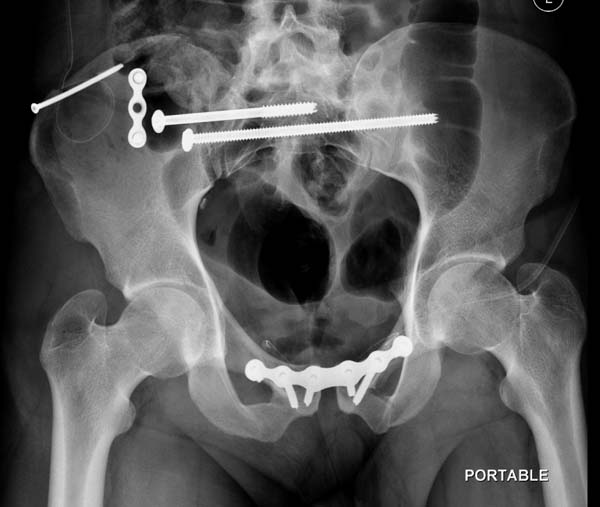

Перелом заднего отдела крыла подвдошной кости доказывает, что задние

связочные элементы подвздошно- крестцового сочленения интактны, и такой

перелом известен как“Сrescent fracture’. Переломы разделяется на 4 типа,

и до фиксации надо хорошо изучить топографию перелома, иначе винт может

попасть в линию перелома и не удержать фиксацию.

Но вам повезло, двумя винтами смогли зацепить и репонировать

переломо-вывих. Обычно такие переломы надо фиксировать спереди или сзади

пластиной или шурупом, т.е. создать дополнительную стабильность крыла,

кроме  перкутанной фиксации.

Здесь примеры фиксации с различными вариантами.... .